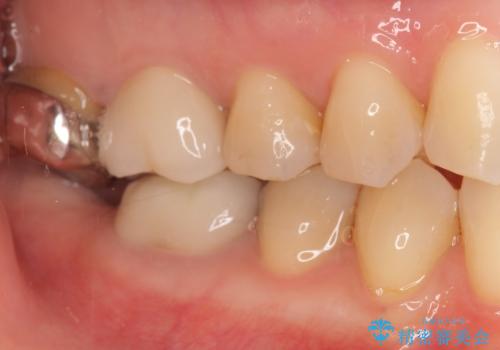

治療後はしみなくなり、違和感のない自然な咬み心地にご満足頂けました。

「割れる心配のないゴールドにしたいけれど、目立ってしまうかしら...」と心配されており、不要に歯質を削合しないよう注意を払い最小限の大きさのインレーを装着したところ、「あまり目立たなくて良かった!」とおっしゃって下さいました。

審美面でセラミックに劣りますが、奥歯の治療には最適な材料です。